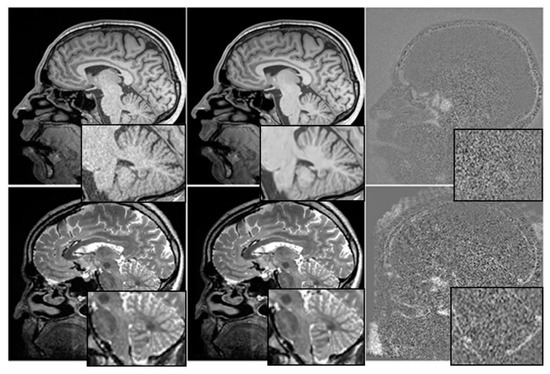

The relationship between cognitive tests, medication, and mental health is depicted graphically in Figure 3. We have investigated the utility of multimodal time-series data in making prognoses about the course of AD.

Figure 3.

Before and After Denoising.

We have used T1-weighted MRI images acquired from a cohort of 100 patients diagnosed with AD and 100 age-matched healthy controls. The MRI images having a resolution of 1 mm × 1 mm × 1 mm and dimensions of 256 × 256 × 160. The intensity values of each pixel in the MRI images ranged from 0 to 255.

Before training the Mayfly optimization algorithm, the MRI images were pre-processed by applying skull stripping, intensity normalization, and spatial normalization using the SPM12 toolbox. The images segmented into grey matter, white matter, and cerebrospinal fluid using the FSL software.